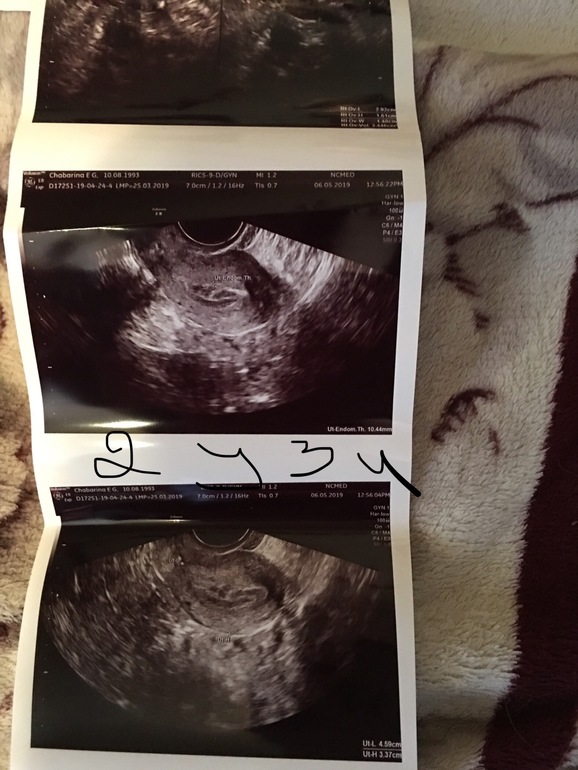

Вопросы про УЗИ, обследования и анализы: что, где, как, когда?Добрый день , я у вас новенькая ) задержка 2 недели , на первой недели была на узи и сейчас . При первом ставили маточную, сейчас внематочную . Помогите разобраться 🙏🏻😩 фото под катом .

Вот на втором узи написано что что то около яичника 21 мм , разве мог так вырасти ?

Хгч да , в 7 дней задержки был 899, на 11 день задержки 598 , выделения были светло коричневые , поехала сразу в больницу - два раза сделали осмотр с зеркалом и пошли почти чёрные с очень мелкими как точка сгустками . Ни капельниц , ни уколов . Ни анализов . Сбежала оттуда сразу на хгч . Всю неделю пью транескам и дюфастон 😟

На узи однозначно идти. Хгч тоже сдайте, пусть будет. Если в трубе и замершая, то будем надеяться, что труба не лопнет. В любом случае, это не нормальная беременность. Хгч на 7 дз должен быть больше. Отпишитесь как узи пройдет. Все пройдет, главное потом проверить трубы хорошо. И найти причину этого.